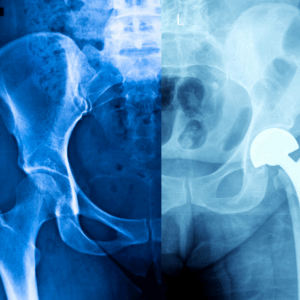

A right knee X-ray produces detailed images of the knee joint, including the femur, tibia, fibula, and patella. Physicians often order this test to evaluate injuries, detect arthritis, monitor post-surgical healing, or investigate persistent joint pain. At Desert Mobile Medical, we bring hospital-grade mobile X-ray technology directly to you—so you get accurate results quickly, privately, and without the hassle of urgent care or hospital visits.

Post-Surgical Follow-Up – To monitor recovery after joint replacement or repair.